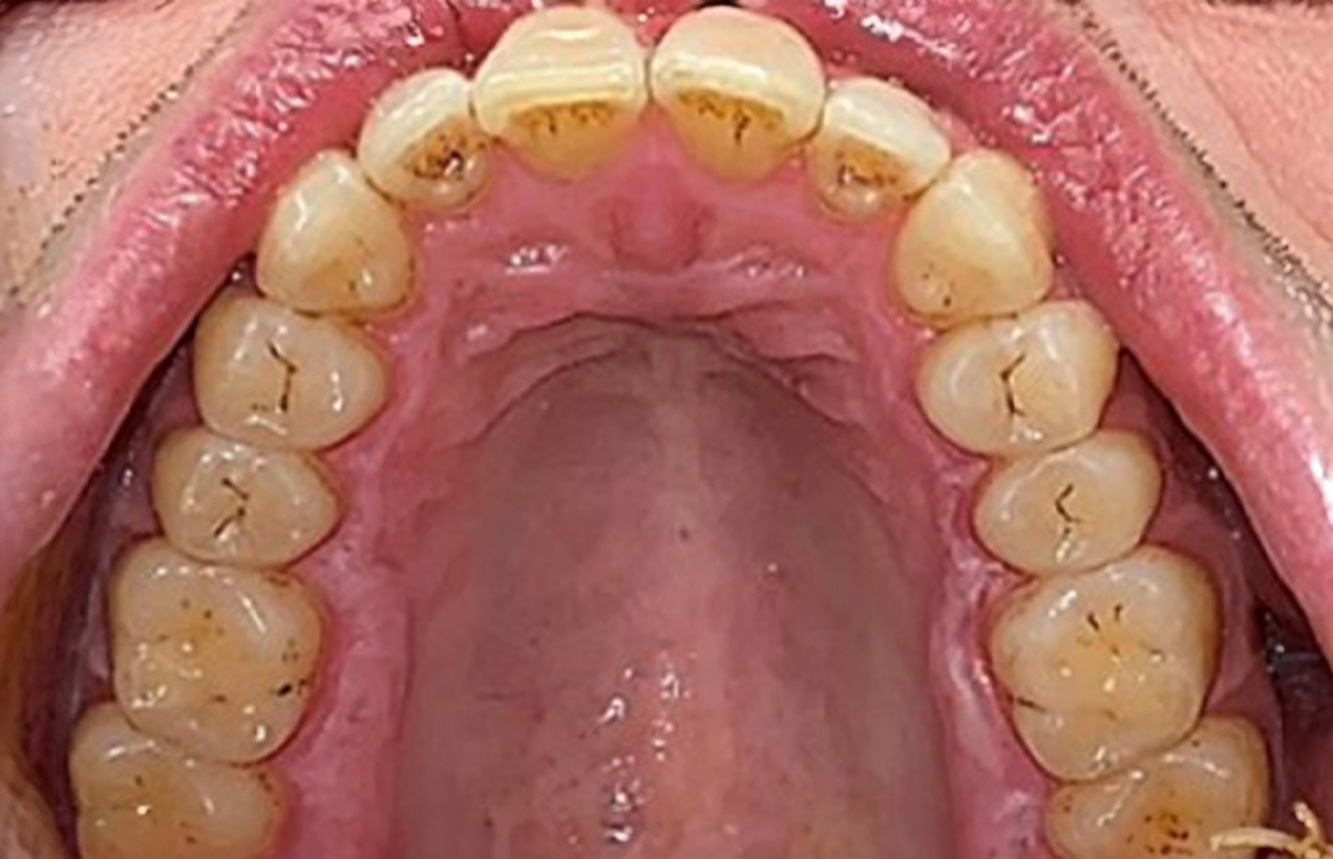

Der (mund)-gesunde Patient mit Implantaten

Der 55-jährige Patient gibt in der Anamnese an, keine Allgemeinerkrankungen zu haben und keine Medikamente einzunehmen. Die Lebensgewohnheiten des Patienten sind ebenfalls unauffällig. Der Patient hat einige zahnärztliche Restaurationen und zwei Implantate (2. und 4. Quadrant). Anhand der aktuellen Befunde lässt sich eine Gingivitis bei stabilem parodontalen Zustand am reduzierten Parodont (Stadium III, Grad A) feststellen. mehr Infos